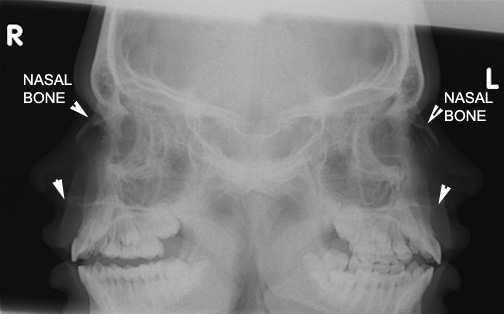

Click the image for labeling.